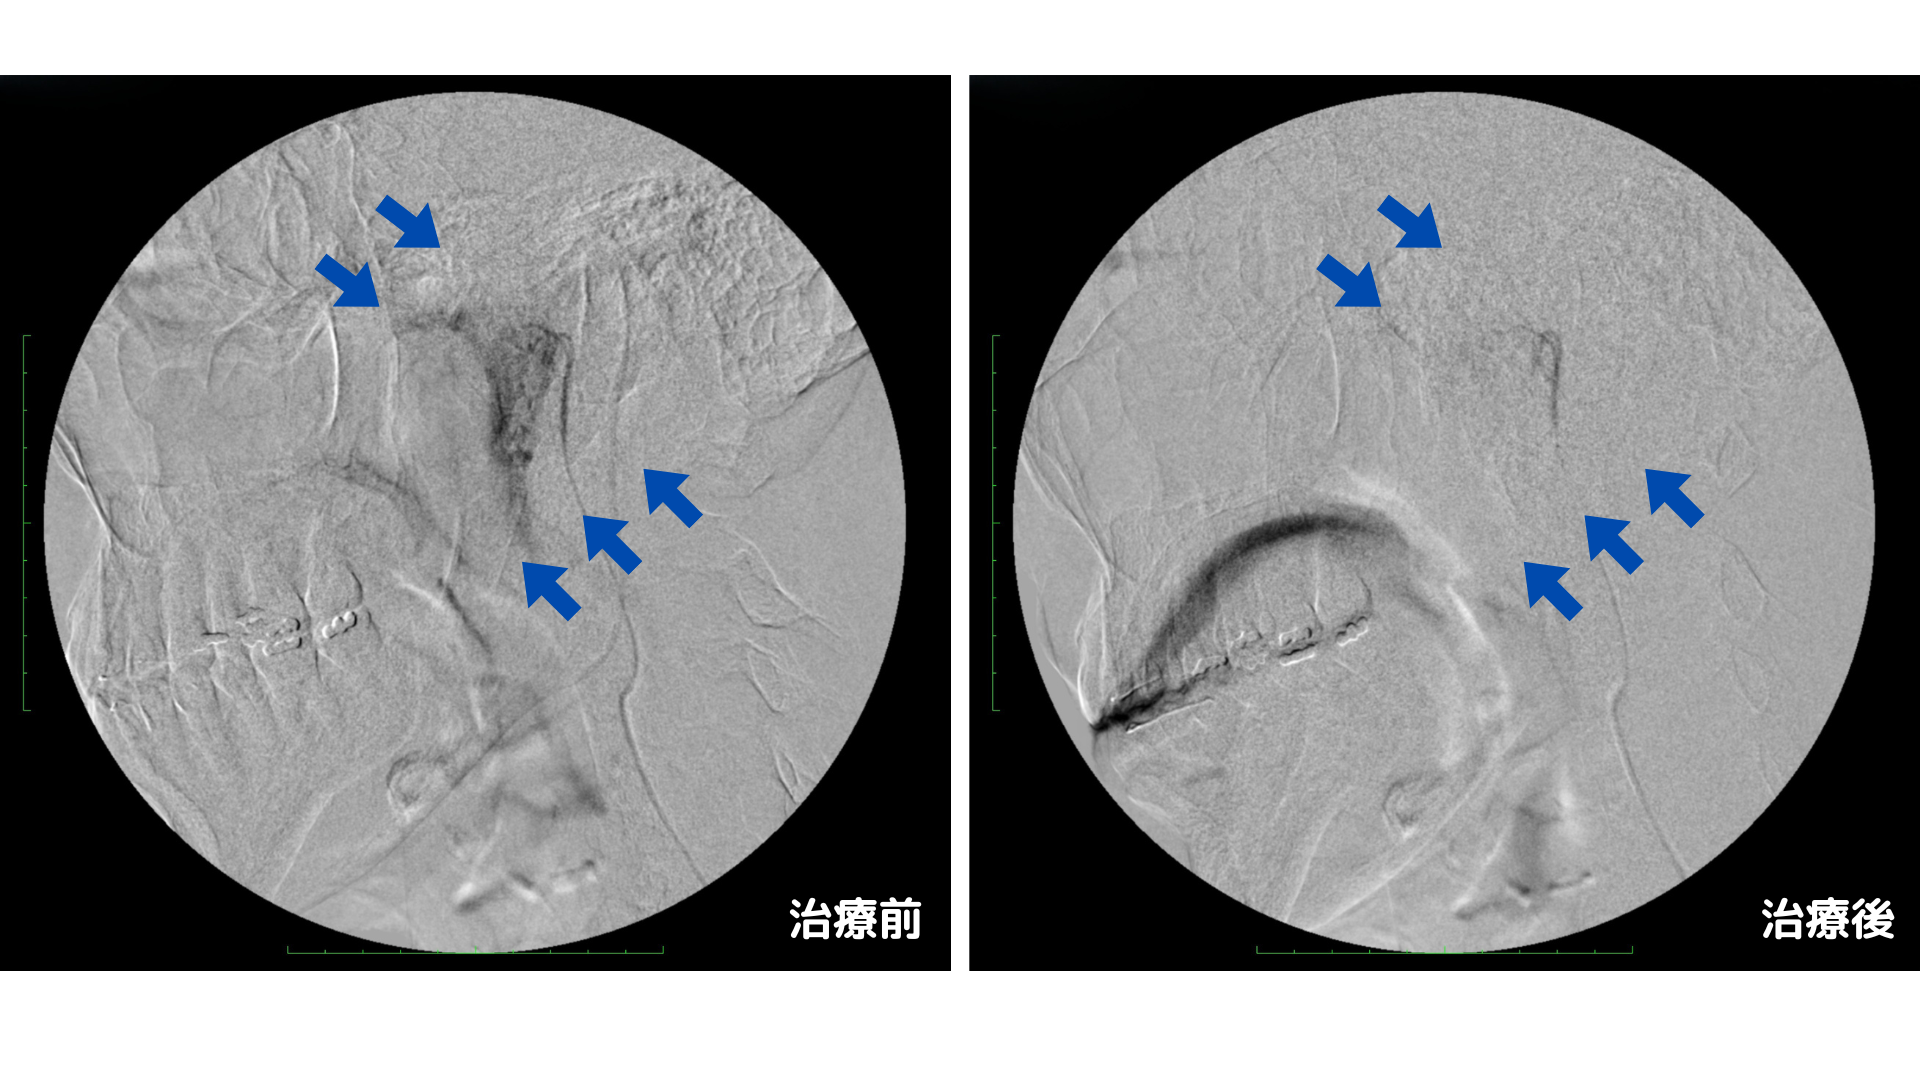

これまでのBスポット療法や投薬で「痛み」や「出血」はある程度治まったものの、声の不調や喉のつっぱり感が残っている原因は、炎症によって増殖した異常な血管(モヤモヤ血管)だと考えられました。

炎症が長引くと、患部には微細な異常血管が増え、神経過敏や組織の硬さを引き起こします。これが「喉が引っ張られる感じ」や「声帯がうまくコントロールできない(声が裏返る)」原因となります。

このモヤモヤ血管を減らすため、日帰りでできるカテーテル治療を行いました。足の付け根から極細のカテーテルを挿入し、咽頭動脈から痛みのある患部へ直接薬を投与し治療しました。